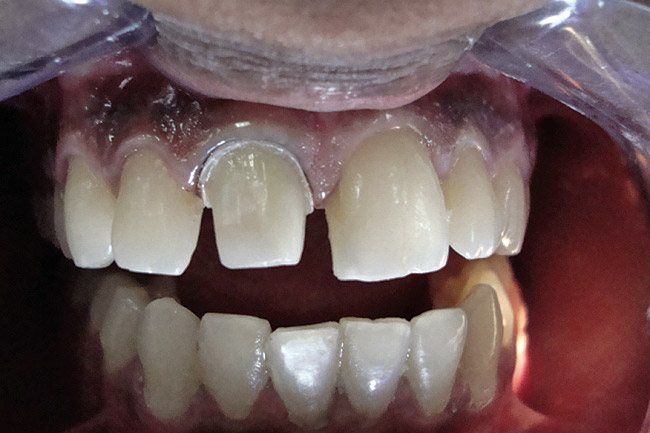

Figure 3  Placement of rubber dam with application of cervical clamp on central incisor for extra retraction.

Figure 3

Figure 4  Final composite restorations with respect to upper right incisors.

Figure 4